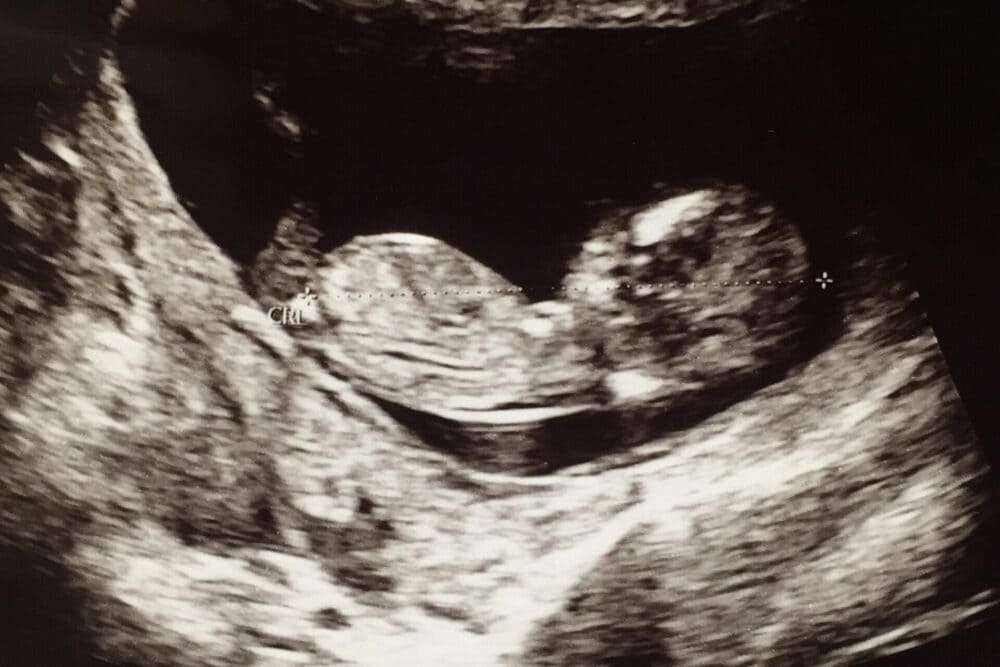

妊娠中は「元気に成長しているか」、お腹の中の赤ちゃんのことがとても気になるかと思います。

胎児のしゃっくりは、妊娠中期から後期にかけて見られる現象です。胎児の横隔膜が不随意に収縮することで起こり、母体ではお腹の中の規則的な軽い動きとして感じます。しゃっくりは通常無害であり、正常な発達の一部です。

しゃっくりは1回数分〜15分程度続くことがあり、母体の腹部では小さな反復的な動きを感じやすいです。しゃっくりは胎児の肺や消化器系の発達に関連している可能性があり、呼吸や飲み込みの練習をしていると考えられています。多くの妊婦さんが経験する一般的な現象ですが、頻度や強さには個人差があります。